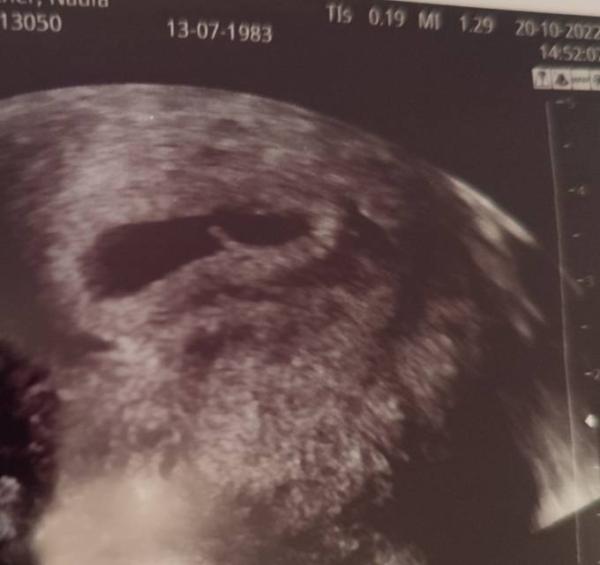

hatte gestern Nachmittag meinen ersten Termin bei einer neuen GynPraxis - war gestern ja erst bei 6+5, aber wurde tatsächlich mit einer Fruchthöhle & Dottersack und einem Embryo mit Herzschlag belohnt

Ein wirklich erleichterndes Gefühl !

Laut Ärztin bin ich einen Tag weiter, aber das ist noch irrelevant.

Ich bin nun das dritte mal schwanger und heute durften mein Mann und ich bei 6+1 nach zwei frühen Fehlgeburten erstmals einen Herzschlag sehen

Mit einen Herzschlag haben wir noch gar nicht gerechnet.